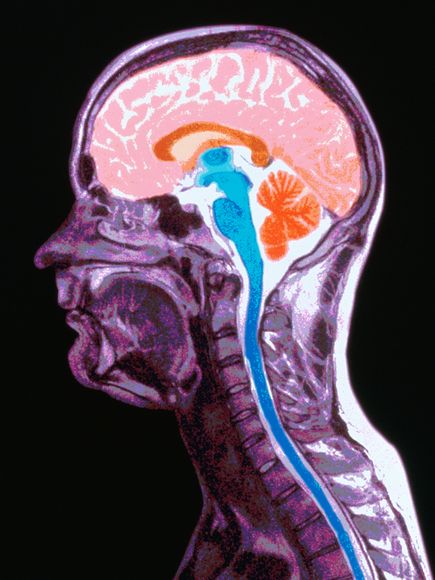

МРТ головного мозга: показания и результаты

Раздел: Визуальный дайджест